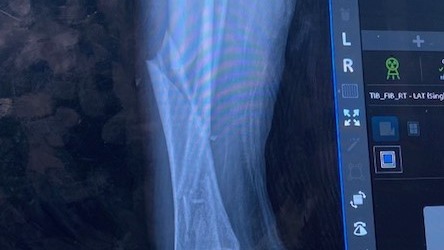

As some of you may have heard, my amazing wife Jennifer broke both the bones in her right leg on March 3rd. Luckily, it wasn't a compound fracture but pretty close to being so. She had an amazing team of surgeons put her back together and now she is on the long road to a healthy recovery. Racquetball is on hold and she is never roller skating again. As we deal with the mountain of medical costs we have dug into our reserves during her work hiatus. Jen is a free-lance, self-employed contractor working on various TV productions in the DFW Metroplex. Since the accident, Jen had to cancel several jobs that she was booked for. Like a lot of us, we are a dual income household so this income loss hurts a bit.